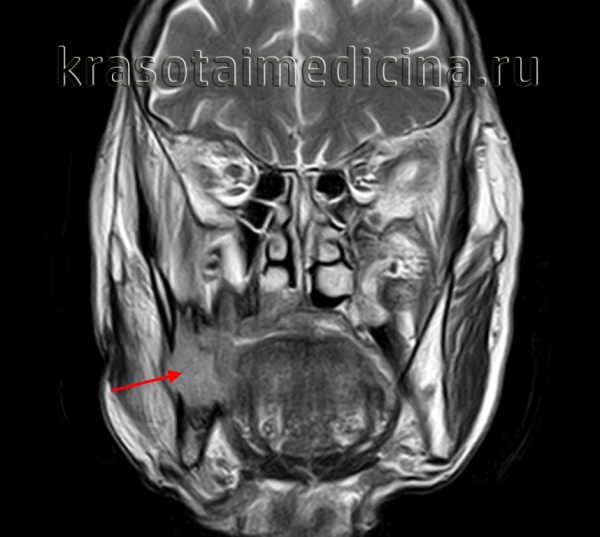

![Амелобластома [11]](/pimg3/opuxoli-kostey-lechenie-26CD06.jpeg)

Амелобластома (Ameloblastoma) — это доброкачественная опухоль, которая развивается из зубообразующих тканей. По мере её роста деформируются черты лица, смещаются и расшатываются зубы.

Амелобластома развивается медленно и бессимптомно, чаще возникает в области угла и ветви нижней челюсти. Почти никогда не вызывает воспаления.

Существует редкий аналог данной опухоли — злокачественная амелобластома, относящаяся к группе одонтогенных раков. Она может давать метастазы в другие органы, например в кости, селезёнку, печень и лёгкие [1] .